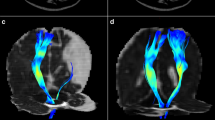

The method for calculating DTI-ALPS is summarized in Fig. 2. The DTI-ALPS index was calculated as the ratio of the mean diffusivity along the x-axis of the projection fiber and association fiber regions of interest (ROIs) to the mean diffusivity along the y-axis and z-axis of the same ROIs (3 mm3) [24]. The ROIs were drawn on the color-coded FA map at the same level as the reference SWI in the left hemisphere since all the participants included in the analysis were right-handed according to previous research [36], while avoiding significantly damaged tissue:

Schematic diagram of the processing of the DTI-ALPS method. A Color-coded fractional anisotropy (FA) map at the lateral ventricle body level demonstrating projection fibers (y-axis, blue) and association fibers (z-axis, green). ROIs are drawn on left projection fibers and association fibers following the course of the medullary vessels using the reference information obtained from SWI. B The ALPS index was calculated after extracting the diffusivity of each ROI along the x-, y-, and z-axes, respectively